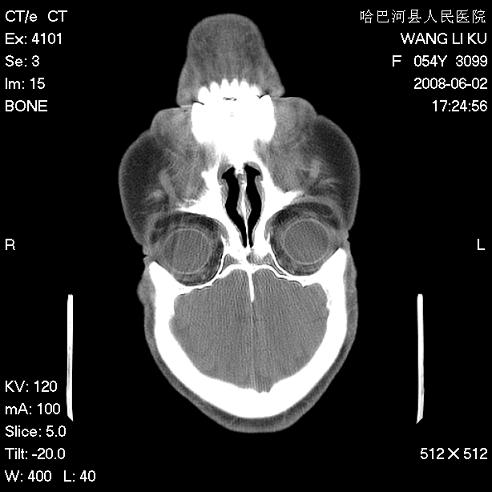

标题: CT13803:反复性鼻塞、流涕一年余 [打印本页]

标题: CT13803:反复性鼻塞、流涕一年余

副鼻窦炎,右上额窦积脓。左眼肌锥内见致密影,视神經受压

1.全组副鼻窦炎2.双侧上颌窦积液

全组副鼻窦炎 肌锥内高密度灶。建议进一步检察检查

1、全组副鼻窦炎。

2、左眼眶肌锥内病变,小血管瘤?建议增强。

1)全副鼻窦炎(左侧上颌窦黏膜下囊肿或息肉)。2)左眼眶肌锥内不规则小结节状软组织密度影;考虑为小血管瘤可能。建议行ct增强扫描检查。

全组副鼻窦炎,左侧肌锥内不规则形软组织肿块影,与眼外肌密度相当,左侧视神经受压,肿块与视神经及眼外肌分界清晰,眼外肌无增粗,眶壁无破坏,球后脂肪间隙不模糊,考虑良性改变,小血管瘤或神经源性肿瘤可能,建议增强扫描。

谢谢,增强扫描做了,眶内病灶与海绵窦同步明显强化,血管瘤